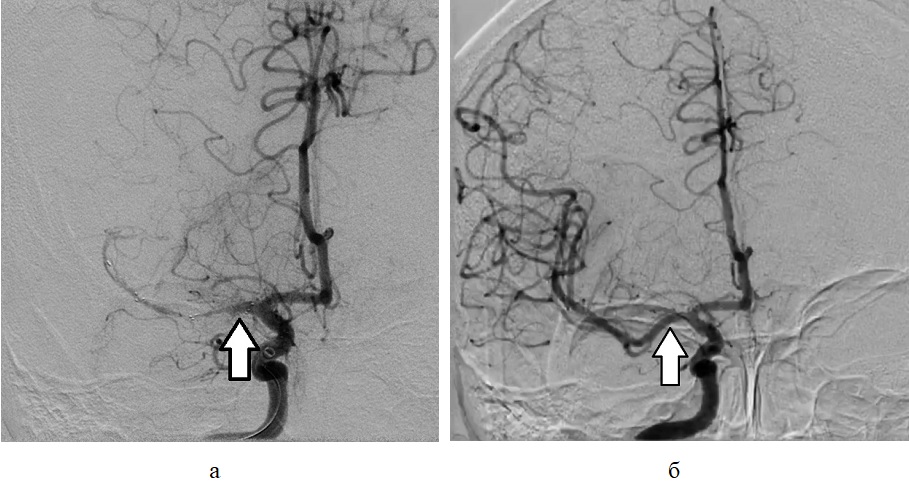

Рисунок 7 - Пациент А., 66 лет, с ишемическим инсультом, осложнившимся геморрагической трансформацией очага ишемии после тромбэкстрации

Примечание: рентгенконтрастная церебральная ангиография во фронтальной проекции: а – Отсутствие контрастирования СМА (стрелка) – тромбоз М1 сегмента СМА; б – Восстановление кровотока в СМА (стрелка) после тромбэкстракции